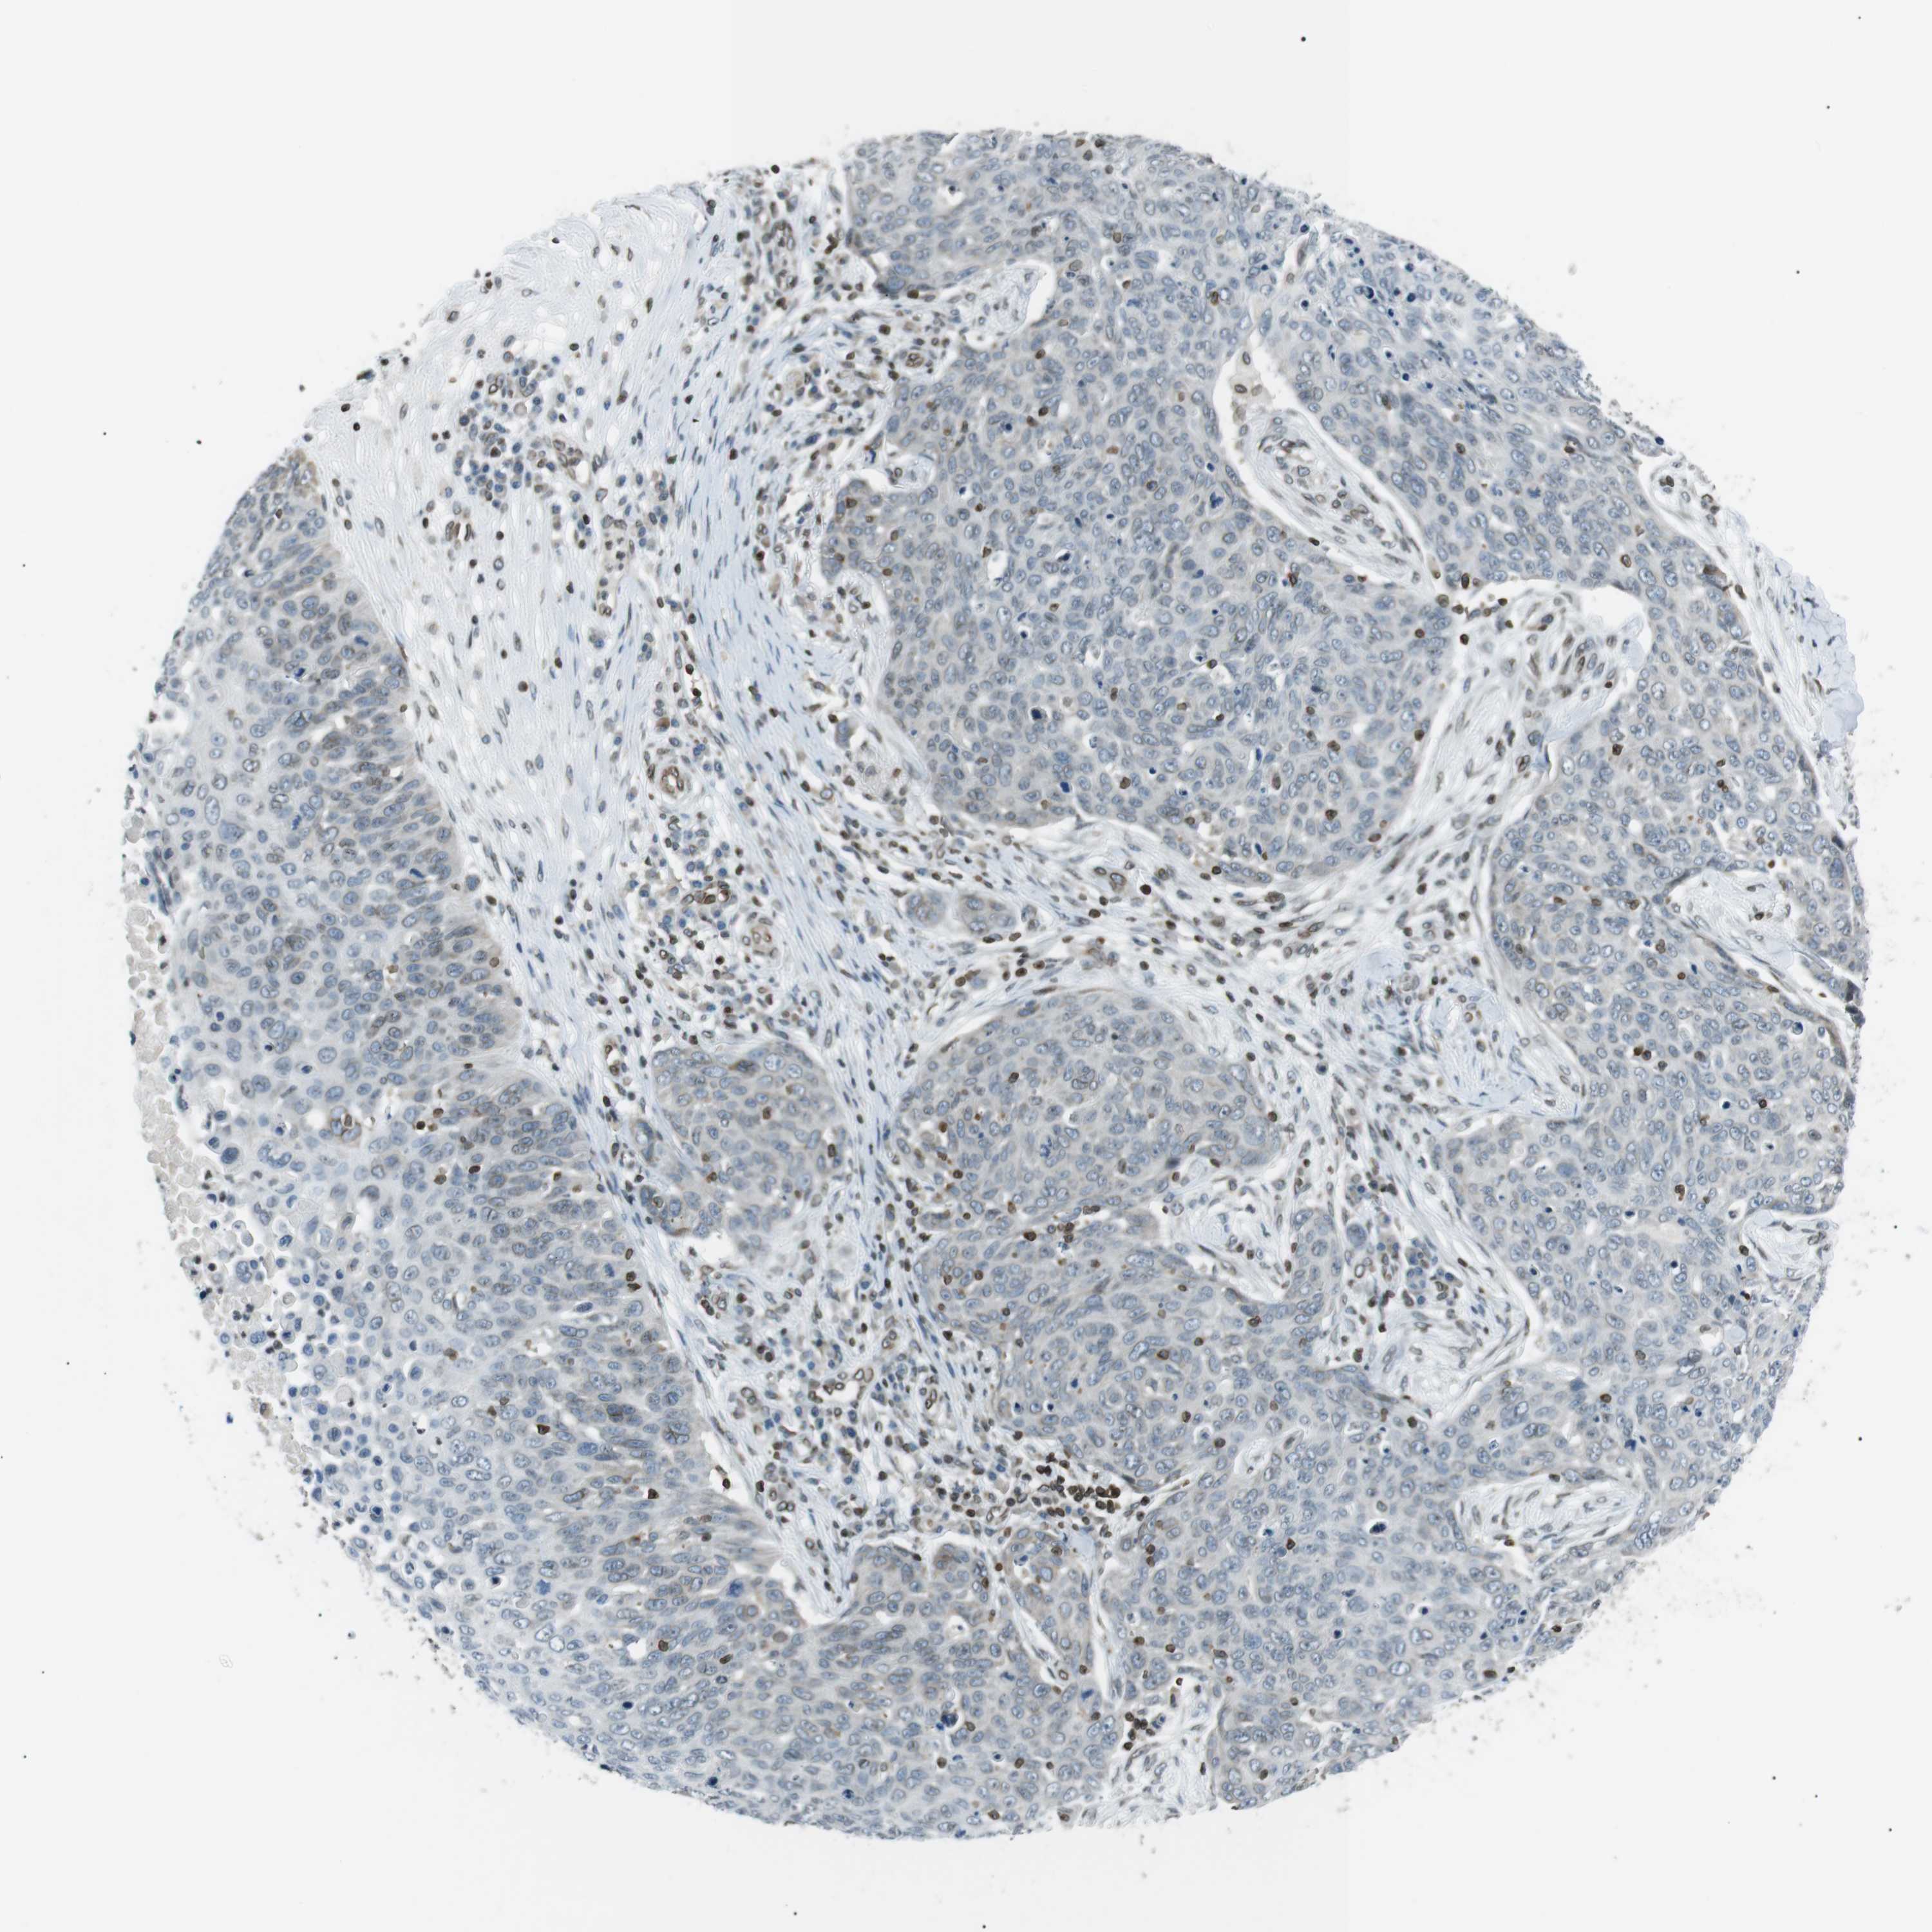

Basal cell and squamous cell cancer

SKIN CANCER - Protein expressioni

A mouse-over function shows sample information and annotation data. Click on an image to view it in a full screen mode. Samples can be filtered based on level of antibody staining by selecting one or several of the following categories: high, medium, low and not detected. The assay and annotation is described here.

Antibody stainingi

Antibody staining in the annotated cell types in the current human tissue is reported as not detected, low, medium, or high, based on conventional immunohistochemistry profiling in selected tissues. This score is based on the combination of the staining intensity and fraction of stained cells.

Each image is clickable and will lead to virtual microscopy that enables deeper exploration of all samples and also displays staining intensity scores, fraction scores and subcellular localization as well as patient and tissue information for each sample.

Antibody HPA000399

Antibody HPA015752

Staining

High

Medium

Low

Not detected

Intensity

Strong

Moderate

Weak

Negative

Quantity

>75%

75%-25%

<25%

None

Location

Nuclear

Cytoplasmic/membranous

Cytoplasmic/membranous,nuclear

Squamous cell carcinoma, NOS

Squamous cell carcinoma, metastatic, NOS

Basal cell carcinoma

Squamous cell carcinoma in situ, NOS

Adnexal tumor, benign